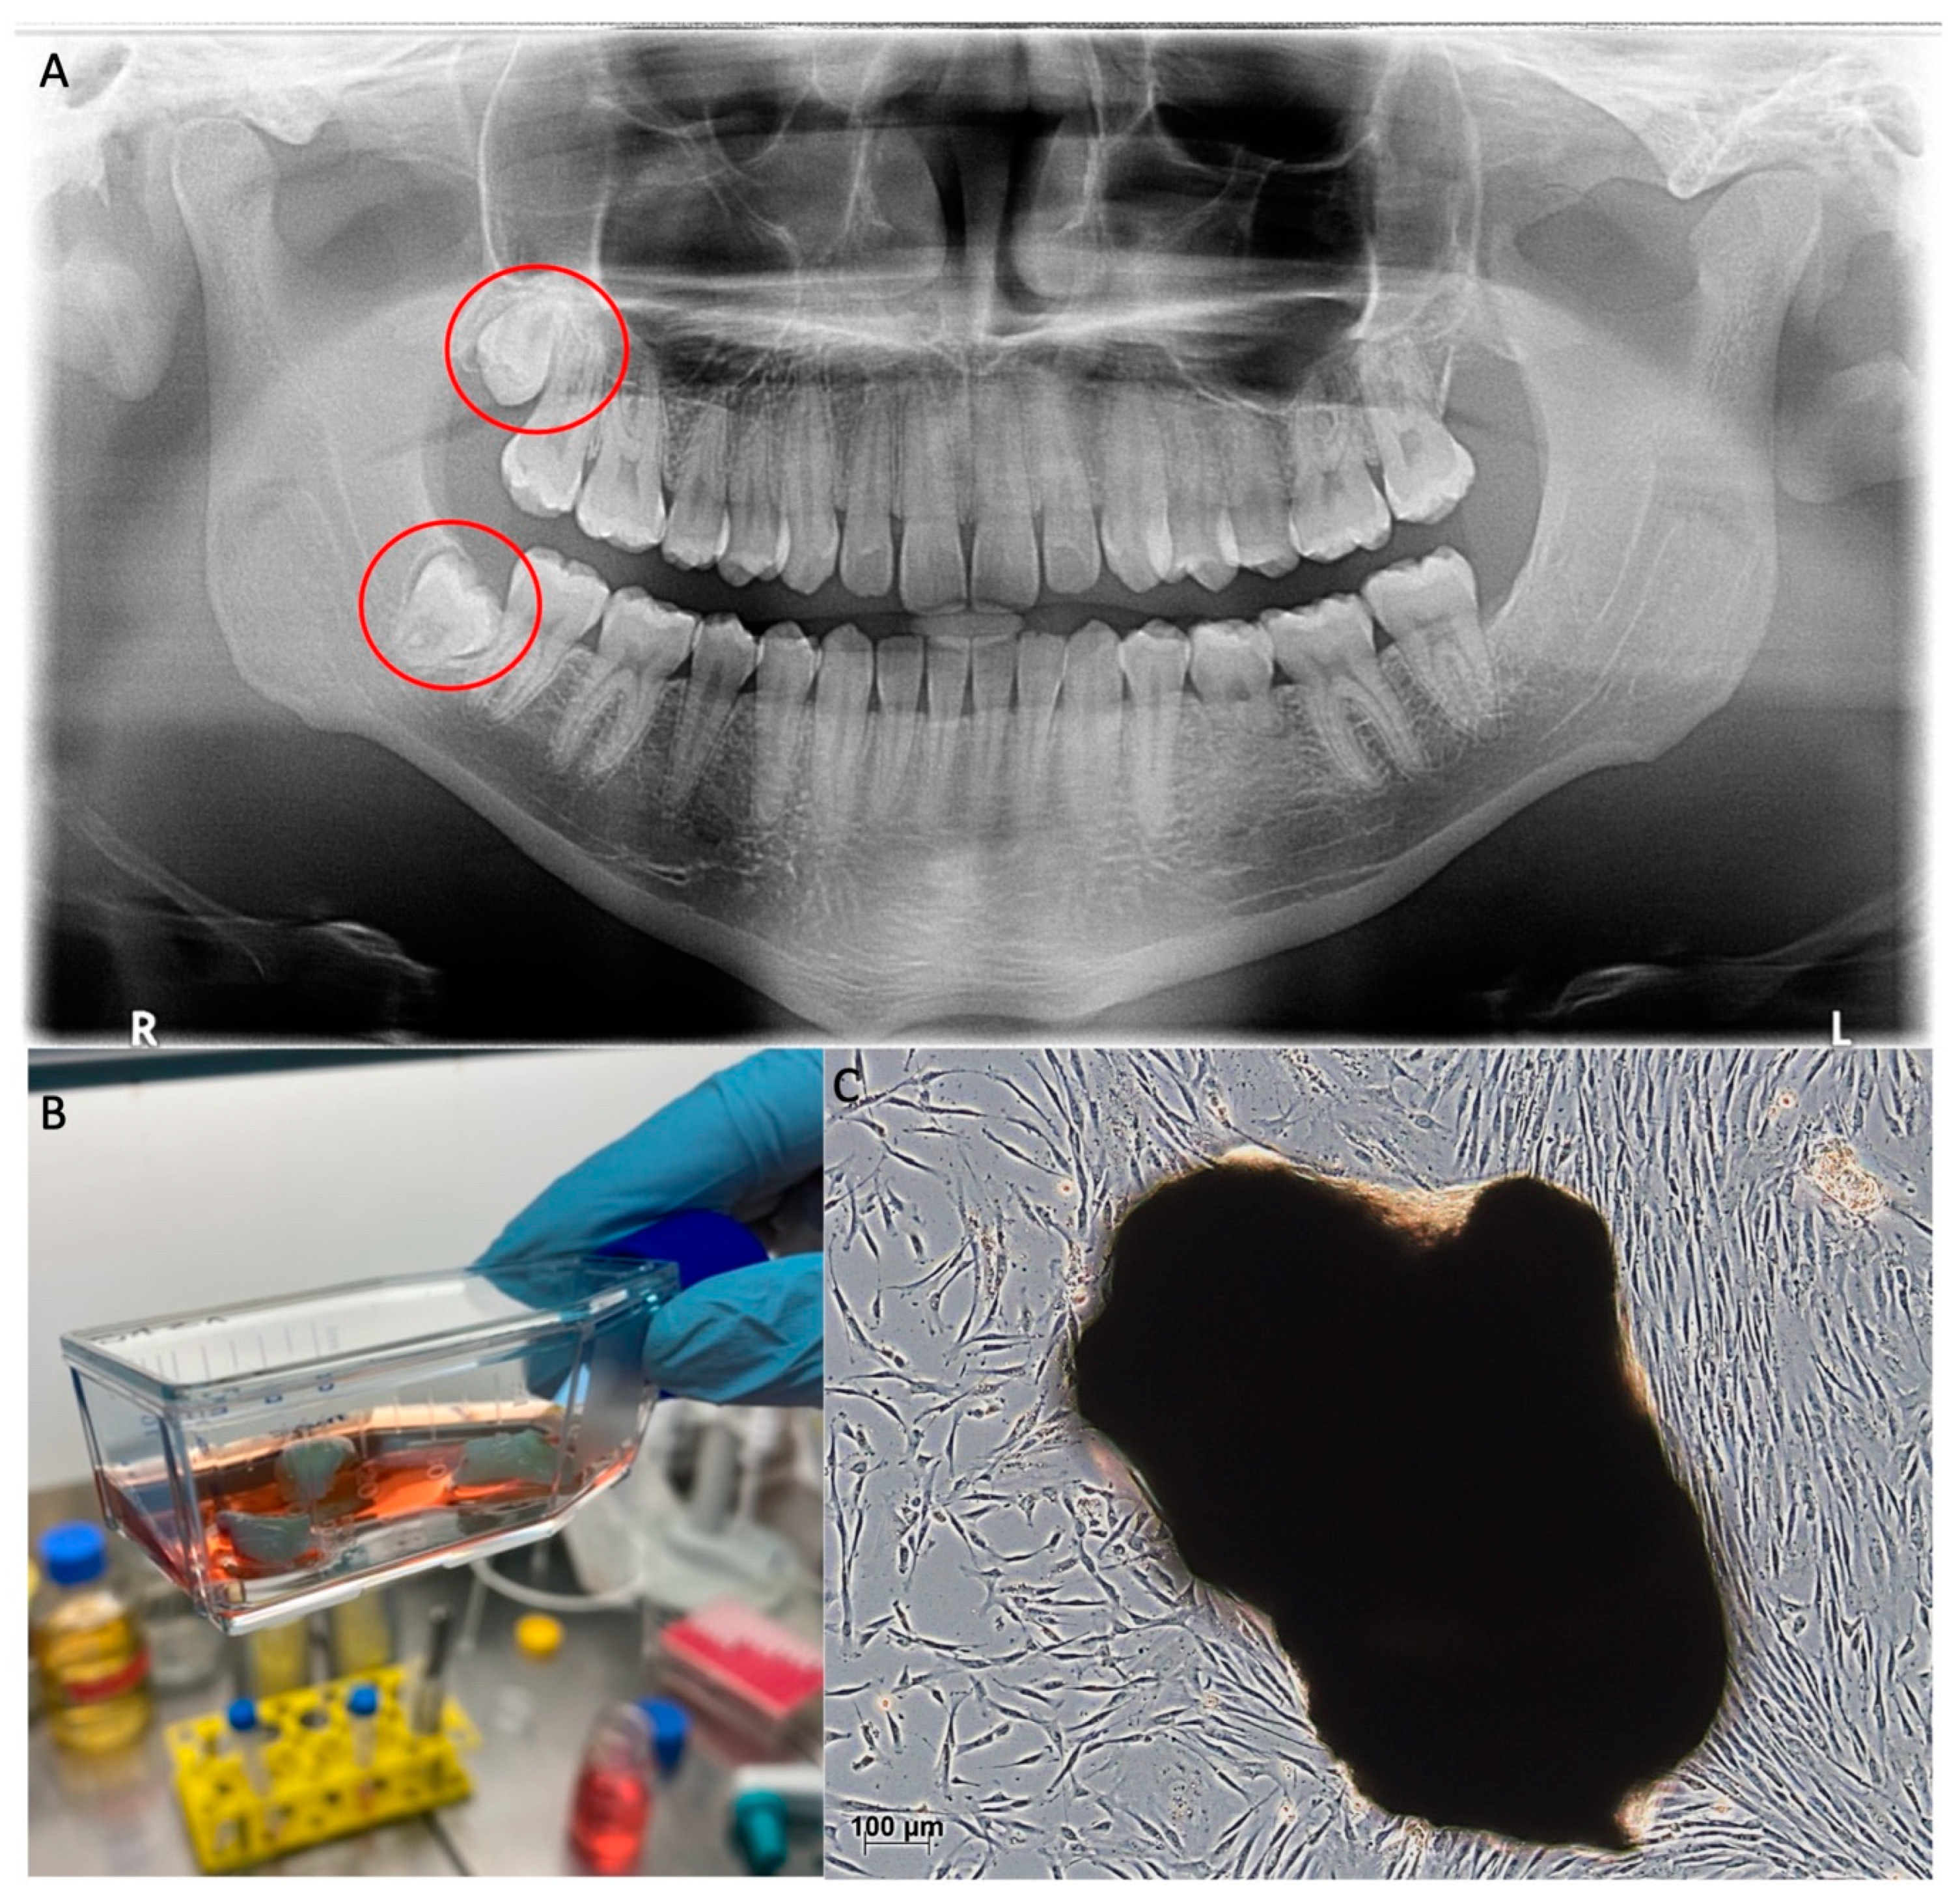

- Gronthos, S.; Mankani, M.; Brahim, J.; Robey, P.G.; Shi, S. Postnatal human dental pulp stem cells (DPSCs) in vitro and in vivo. Proc. Natl. Acad. Sci. USA 2000, 97, 13625–13630. [Google Scholar] [CrossRef] [PubMed]

- American Association of Oral and Maxillofacial Surgeons. Available online: https://www.aaoms.org/images/uploads/pdfs/management_third_molar_supporting_information.pdf (accessed on 10 August 2021).

- Pilbauerová, N.; Suchánek, J. Cryopreservation of Dental Stem Cells. Acta Med. Hradec Kral. 2018, 61, 1–7. [Google Scholar] [CrossRef]